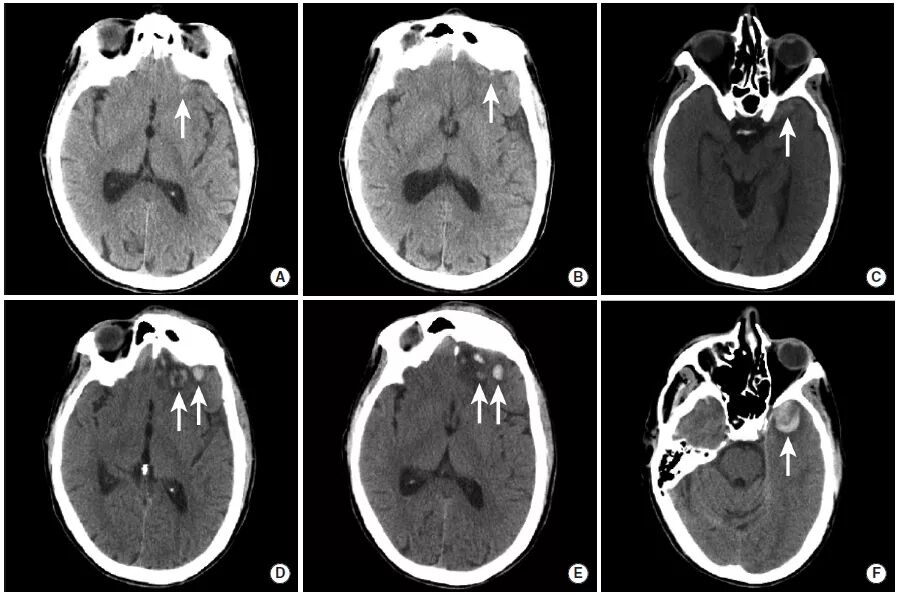

图5

本图显示了出血性脑实质挫伤随时间的演化过程。图A~C为接诊患者时进行的检查,图D~F为2小时之后的复查。患者左侧眶额叶和左前颞叶可见多发小出血灶。在后续成像中,挫伤导致的出血出现了扩大。